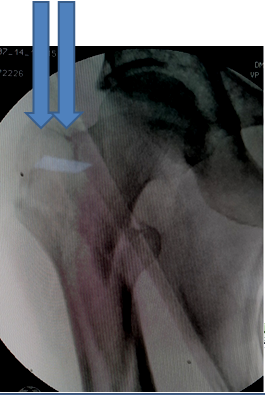

Indications (Figure 1)

1. Unstable IT fractures

1. Comminuted

2. Reverse oblique

3. Subtrochanteric extension

2. Associated shaft fracture

Figure 1 PFN in IT fractures.